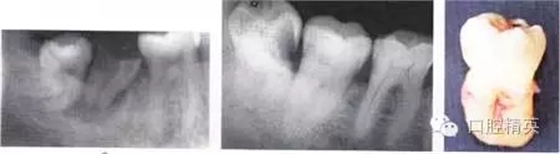

圖6-4 以上類型的下頜第三磨牙由于根阻力大,一般需要分根才能拔除

A.多根牙 B。超長根 C。牙根向遠(yuǎn)中彎曲 D。兩根環(huán)抱 E。根分叉大 F,根端肥大 G。彎根 H.U型根(X線片及離體牙)

A

B

C

D

E

F